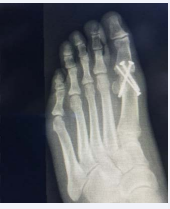

Before any treatments are offered a series of radiographs should be taken to assess the pathology of the first MPJ. This usually consists of the lateral, anteroposterior, and the medial oblique views of the affected foot. The AP view allows the practitioner to assess the joint space, while the lateral and MO views will show any associated spurring around the joint as well as the joint space. Occasionally loose bodies or sub chondral cysts are seen in any view taken. Sclerosis of the bone may also be seen on the radiographic studies since this is one of the ways that the bone tries to heal itself (Figure 1-4).

Figure 1: Pre operative Radiographs. This is a radiograph of a patient that presented to the clinic with a previous attempt at a 1st MPJ fusion that has failed. The patient elected to undergo a revisional procedure with the Arthrosurface total implant.